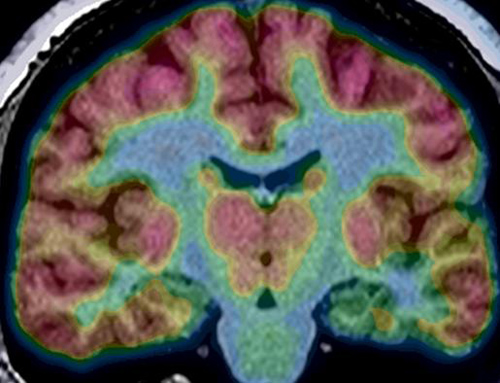

Epilepsy. A PET scan of a brain from a patient with epiepsy, between seizures. The red indicates healthy tissue. On the right side of the image, there is less red in the mesial temporal area. This is hypometabolism, reflecting decreased brain function in the area where seizures begin. Image credit: University of California